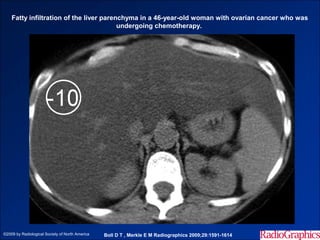

Hình ảnh trên CLVT

- Trước tiêm, tỷ trọng gan < tỷ trọng lách 10 HU.

- Các mạch máu trong gan hiện rõ.

- Sau tiêm, tỷ trọng gan < tỷ trọng lách 25HU or < tỷ trọng cơ.

Fatty infiltration of the liver parenchyma in a 46-year-old woman with ovarian cancer who was

undergoing chemotherapy.

©2009 by Radiological Society of North America   Boll D T , Merkle E M Radiographics 2009;29:1591-1614